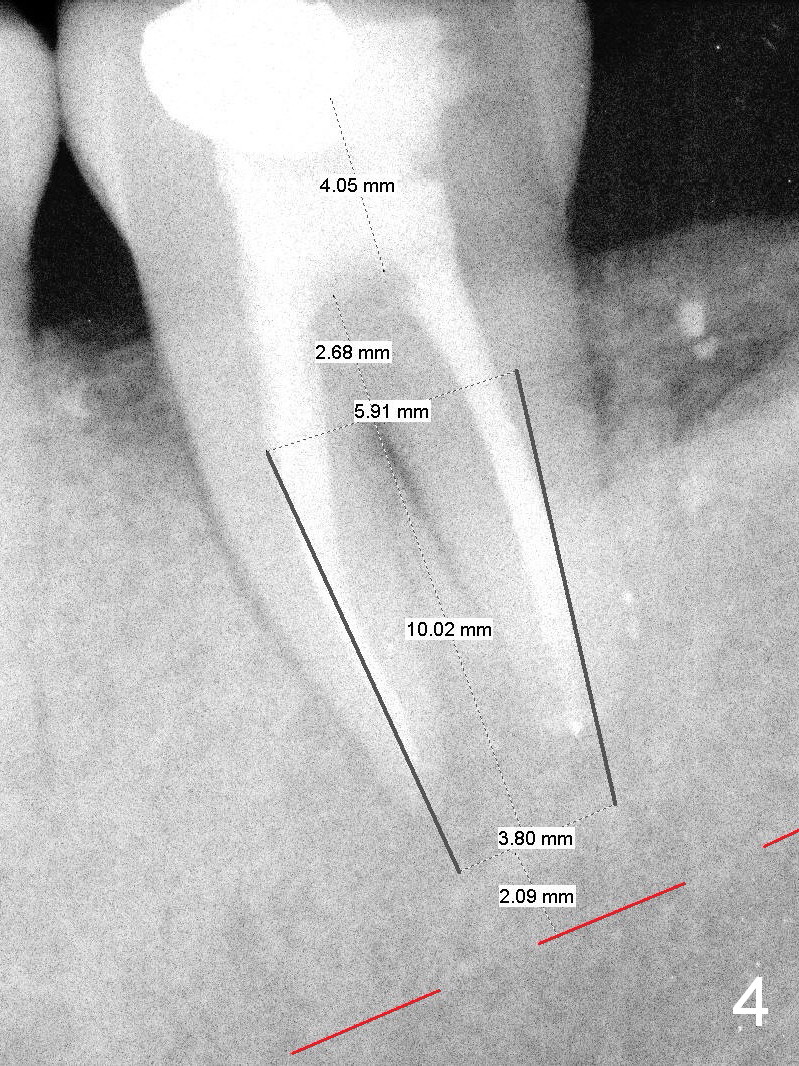

A 55-year-old man must be a dental phobic. With a fistula (Fig.1 <) and large radiolucency associated with the lower left 2nd molar, he postponed root canal therapy for 2 years and 8 months (Fig.2). Later he refused to have crown for the tooth. Three years and 5 months later, the radiolucency seems to have been resolved (Fig.3), but the tooth has fractured with buccal infection. The patient is unwilling to accept treatment of extraction (no antibiotic socket treatment) and immediate implant (Fig.4).